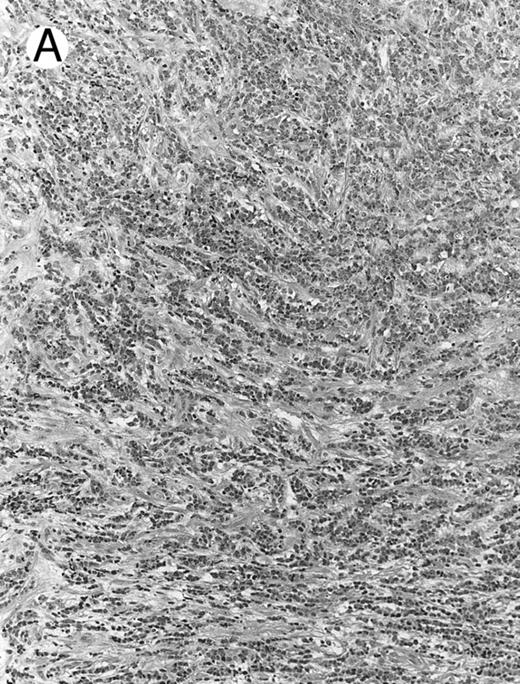

Blastoid NK cell lymphoma (case no. 40). (A) Biopsy shows a diffuse lymphomatous infiltrate with a prominent single-file pattern. (B) The neoplastic cells are medium-sized and possess fine chromatin. Mitotic figures are seen. There is remarkable resemblance to myeloid leukemic infiltration.